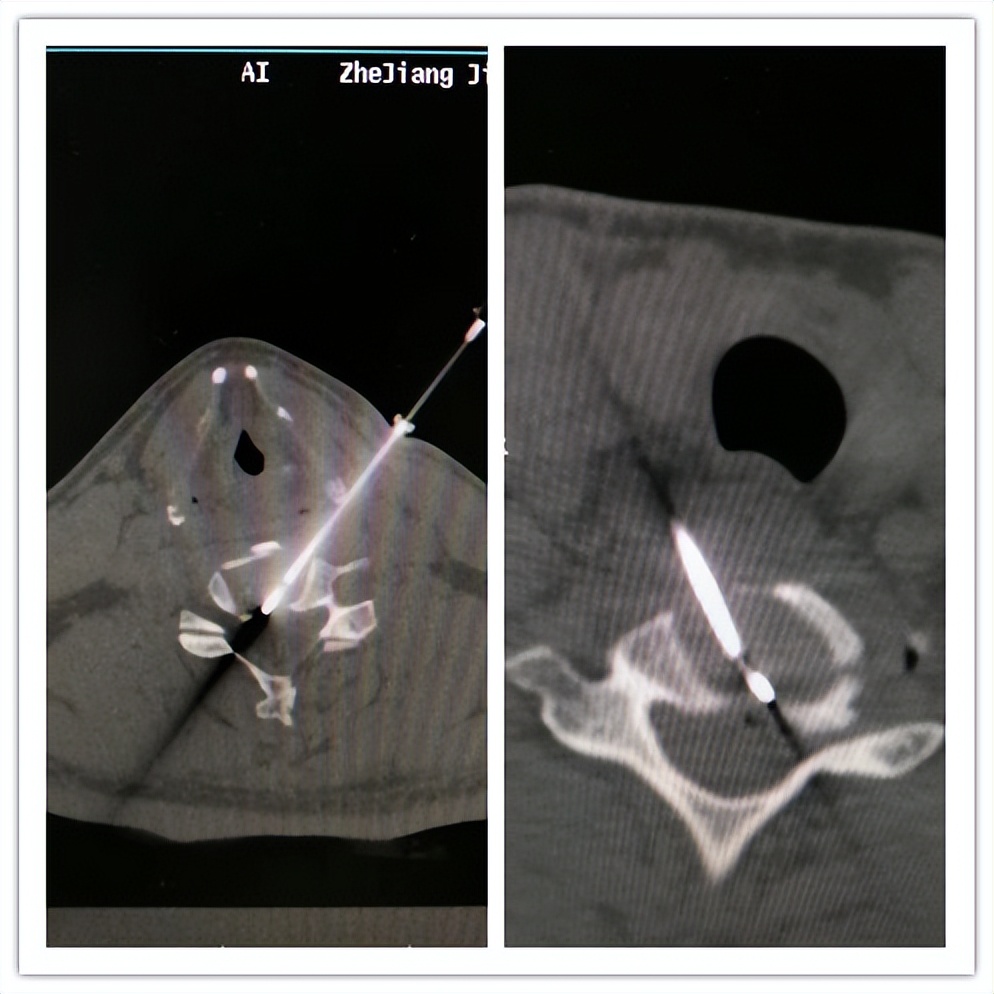

(腰椎间盘突出症:腰椎间盘射频热凝+臭氧消融)

(腰椎间盘突出症:腰椎间盘等离子)

(腰椎间盘突出症:椎间孔镜下腰椎间盘髓核摘除)